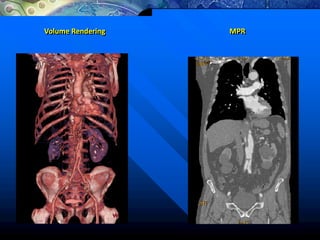

Volume Rendering MPR

Volume Rendering

Reformatações Volumétricas